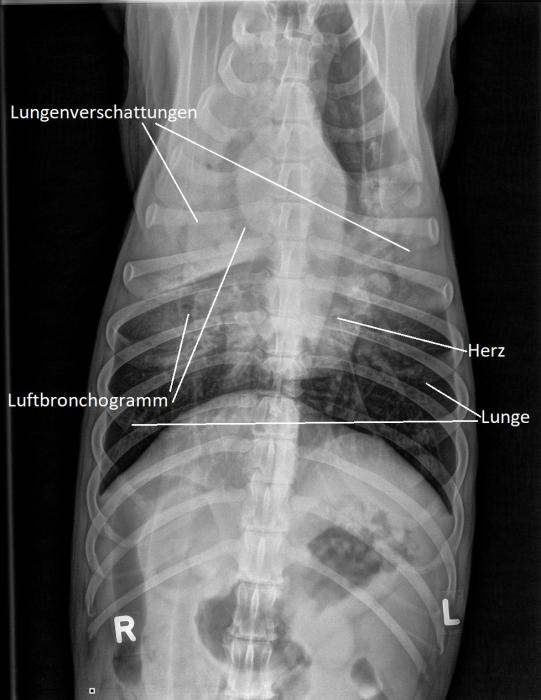

Leider bessert sich Asky's Zustand nicht wirklich, und die Hündin wird erneut vorgestellt. Nun werden Lungenröntgen angefertigt, die das ganze Ausmass des Problemes ans Licht bringen: Weite Teile der Lunge des Hundes erscheinen auf dem Röntgenbild weiss - hier ist die Luft durch Flüssigkeit oder Gewebe ersetzt worden. Wie Bäume im Nebel sind auch sogenannte Luftbronchogramme sichtbar - nur die grossen Bronchien enthalten noch Luft. Ganz offensichtlich hat sich Asky eine fulminante Lungenentzündung geholt!